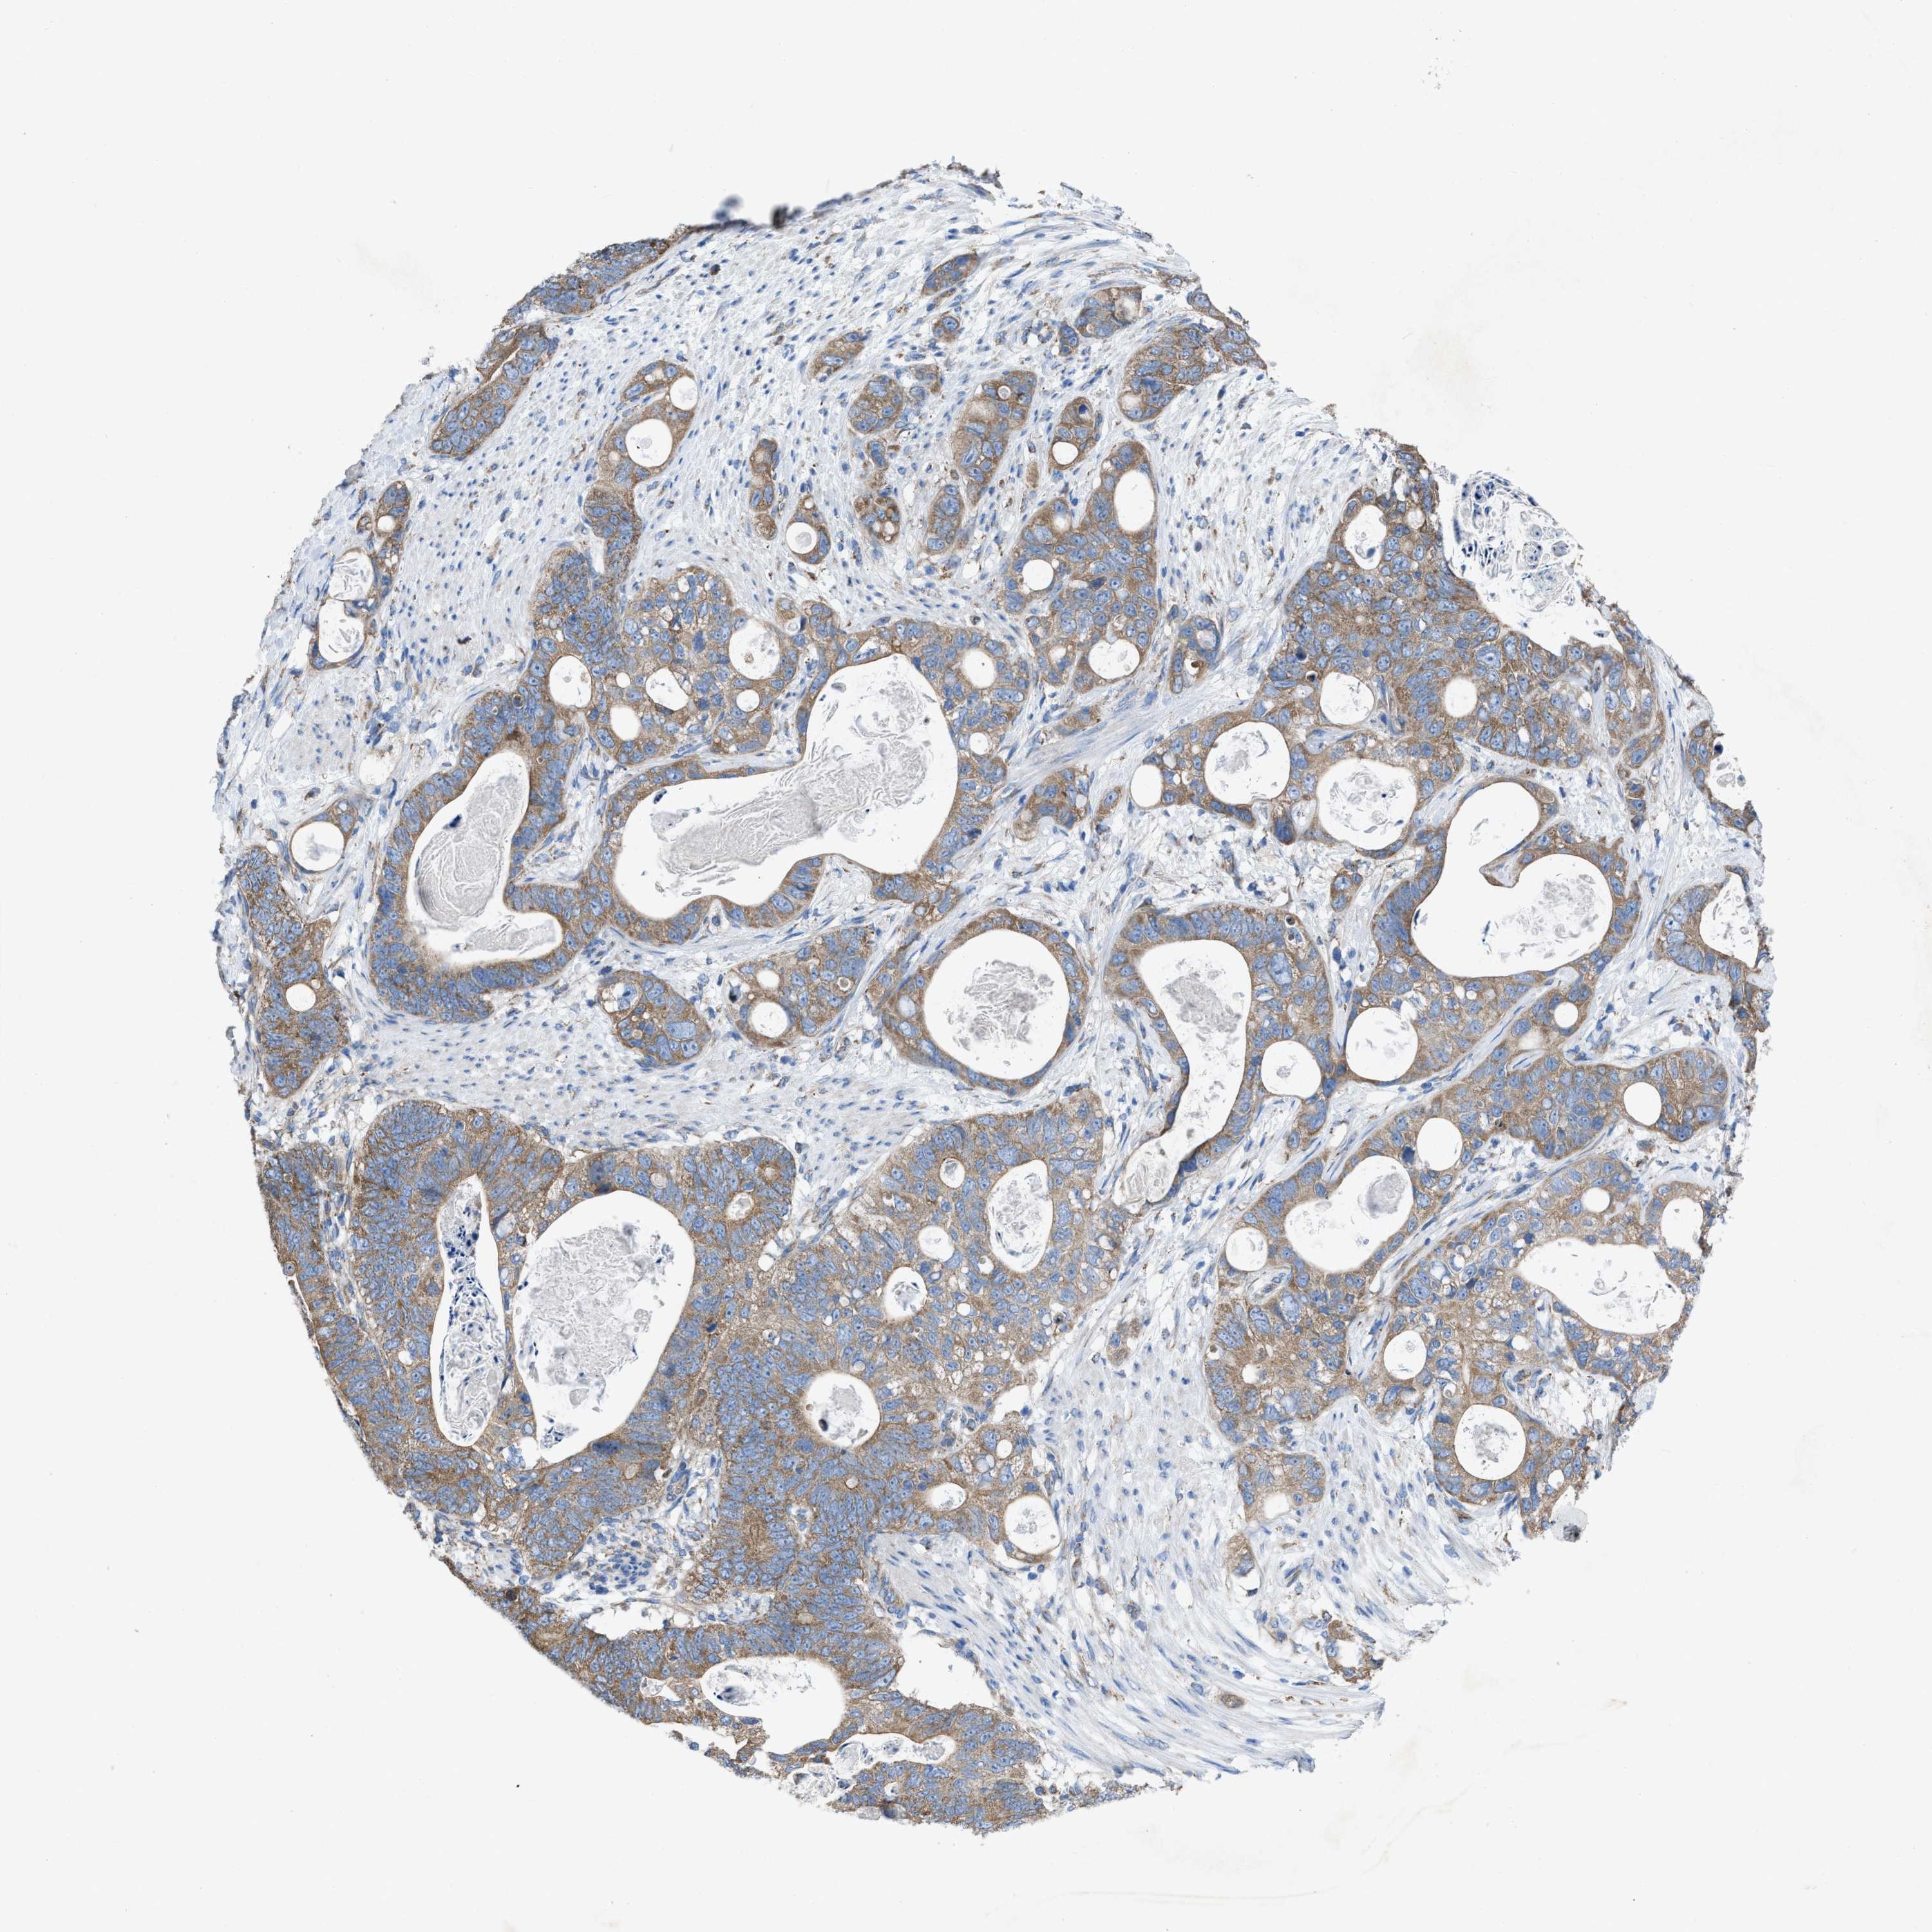

STOMACH CANCER - Protein expressioni

A mouse-over function shows sample information and annotation data. Click on an image to view it in a full screen mode. Samples can be filtered based on level of antibody staining by selecting one or several of the following categories: high, medium, low and not detected. The assay and annotation is described here.

Antibody stainingi

Antibody staining in the annotated cell types in the current human tissue is reported as not detected, low, medium, or high, based on conventional immunohistochemistry profiling in selected tissues. This score is based on the combination of the staining intensity and fraction of stained cells.

Each image is clickable and will lead to virtual microscopy that enables deeper exploration of all samples and also displays staining intensity scores, fraction scores and subcellular localization as well as patient and tissue information for each sample.

Antibody HPA019179

Staining

High

Medium

Low

Not detected

Intensity

Strong

Moderate

Weak

Negative

Quantity

>75%

75%-25%

<25%

None

Location

Nuclear

Cytoplasmic/membranous

Cytoplasmic/membranous,nuclear

Adenocarcinoma, NOS